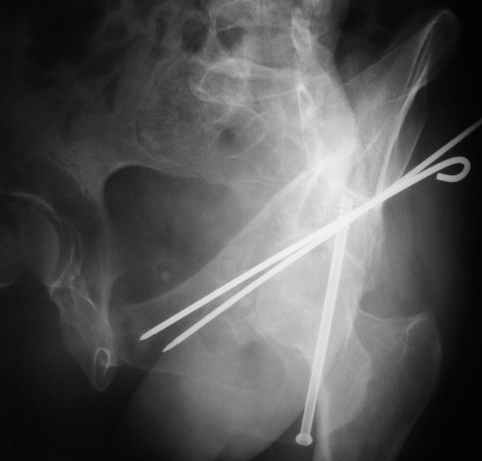

Anatoly F Lazarev 03 Сентябрь 2004, 22:18

Женя! Класный перелом. Отлично репонируется изнутри таза, но лучше фиксированть сзади. Классический перелом для двустороннего доступа.

Однако есть альтернатива. Репозиция из подвздошного доступа тазовыми щипцами с разнодлинными браншами или тазовым пистолетом, а фиксация задней колонны через седалищный бугор или тазрвыми винтами 4,5 или каннюлированными 6,5 или 7,3. По-моему я посылал на ортофорум такой снимок, когда жаловался на ишемический неврит седалищного нерва через сутки после операции. Не забудь про шейку бедра - мне кажется будет хорош длинный PFN любой фирмы, какую ты найдешь, а нет так UFN + miss a nail, как это здорово делают мои земляки - Ебурбуки. Пока.

27.01.04

02.02.04

10.02.04

12.04.04

02.06.04